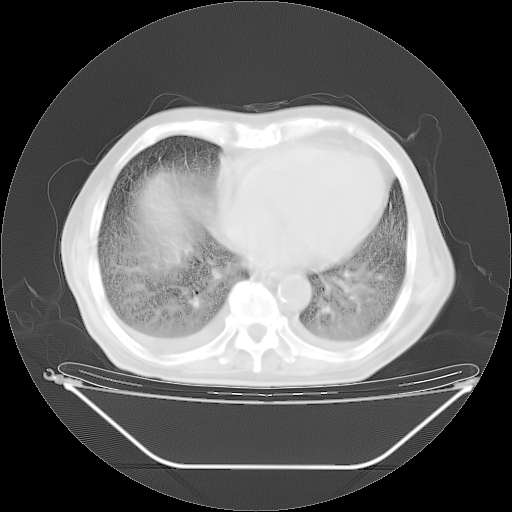

今天复查肺部CT,发现双肺广泛磨玻璃样改变。所以我把3月19日和5月9日相隔50天的肺部CT上传。请大家会诊。

2009年3月19日肺部CT片。

5月9日肺部CT(在4月27日齐鲁医院肺部CT描述部分肺组织磨玻璃样改变,12天后肺组织广泛磨玻璃样改变)